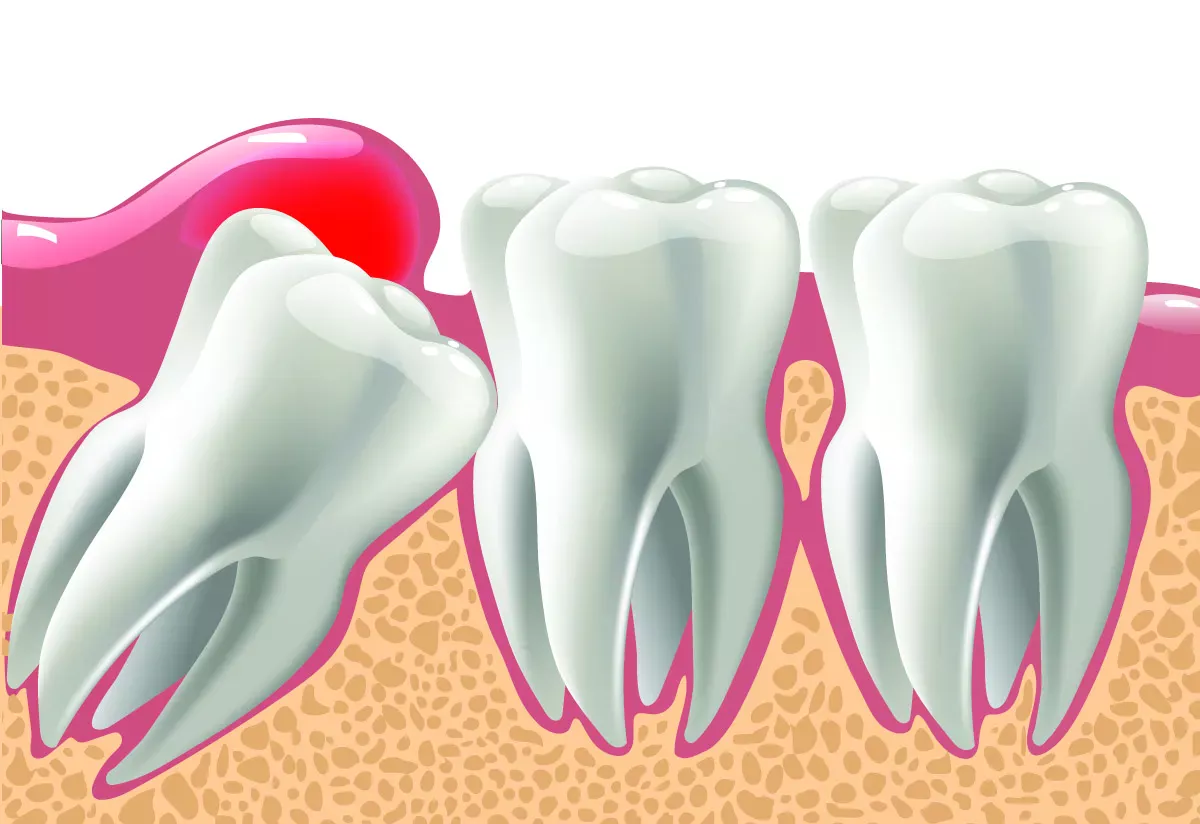

Partially retained wisdom teeth

If wisdom teeth try to break through when there is actually no room in the mouth, this can cause severe pain. The wisdom tooth then not only presses against the gum that stretches over it, but also against the neighbouring tooth. It can happen that the neighbouring molar tooth hurts terribly, even though there is no caries or root inflammation. This is referred to as a "partially retained wisdom tooth": The tooth is still partially under the gum and cannot break through. A kind of gum cap often forms over the tooth. This cap can become inflamed very easily because it is difficult to reach with a toothbrush and provides an ideal breeding ground for bacteria.

Impacted wisdom teeth

If the wisdom teeth do not grow into the mouth at all, but remain in the jaw, they are referred to as "impacted wisdom teeth". People with impacted wisdom teeth often have no symptoms. However, if the wisdom tooth sits at an angle in the jaw and presses on a neighbouring tooth, it can damage the tooth. This can result in root caries, bone loss in the jaw or the teeth shifting due to the pressure.